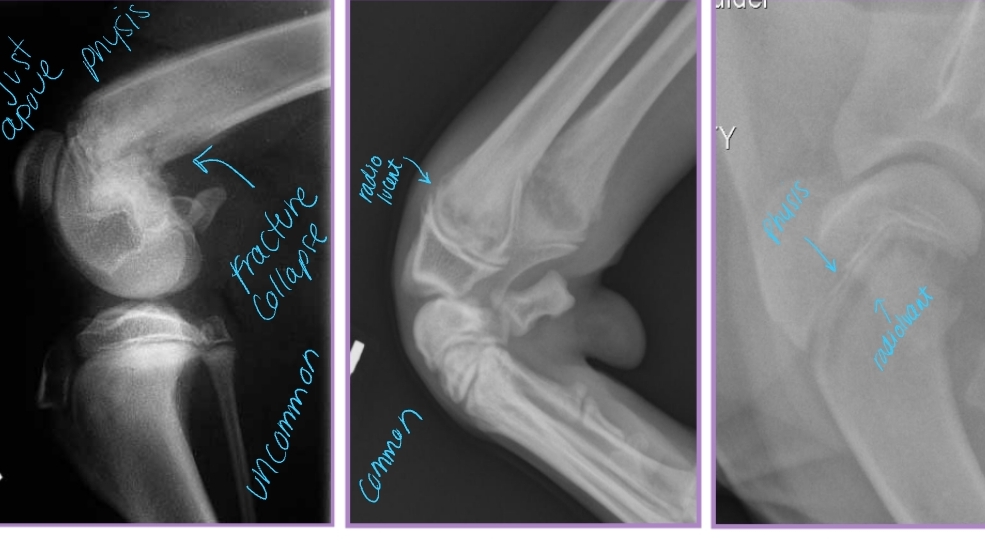

Ununited Anconeal Process

Et: Anconeal process of ulna fails to unite with proximal ulnar metaphysis

Failure of endochondral ossification, Joint incongruity

Hereditary, environmental, hormonal factors

Sig: Large breeds, GSD, Male > female, 5-12 months

Dt: Radiographs FLEXED lateral!

Osteophytes, Effusion, Anconeal process fragment, Joint incongruity

Elbow Incongruity

Et: Asynchronous growth of radius and ulna

Dt: radiographs

Tx: Corrective ulnar ostectomy (short radius syndrome)

Redistribute stress in joint

Allow bone alignment at joint level

Decrease joint stress